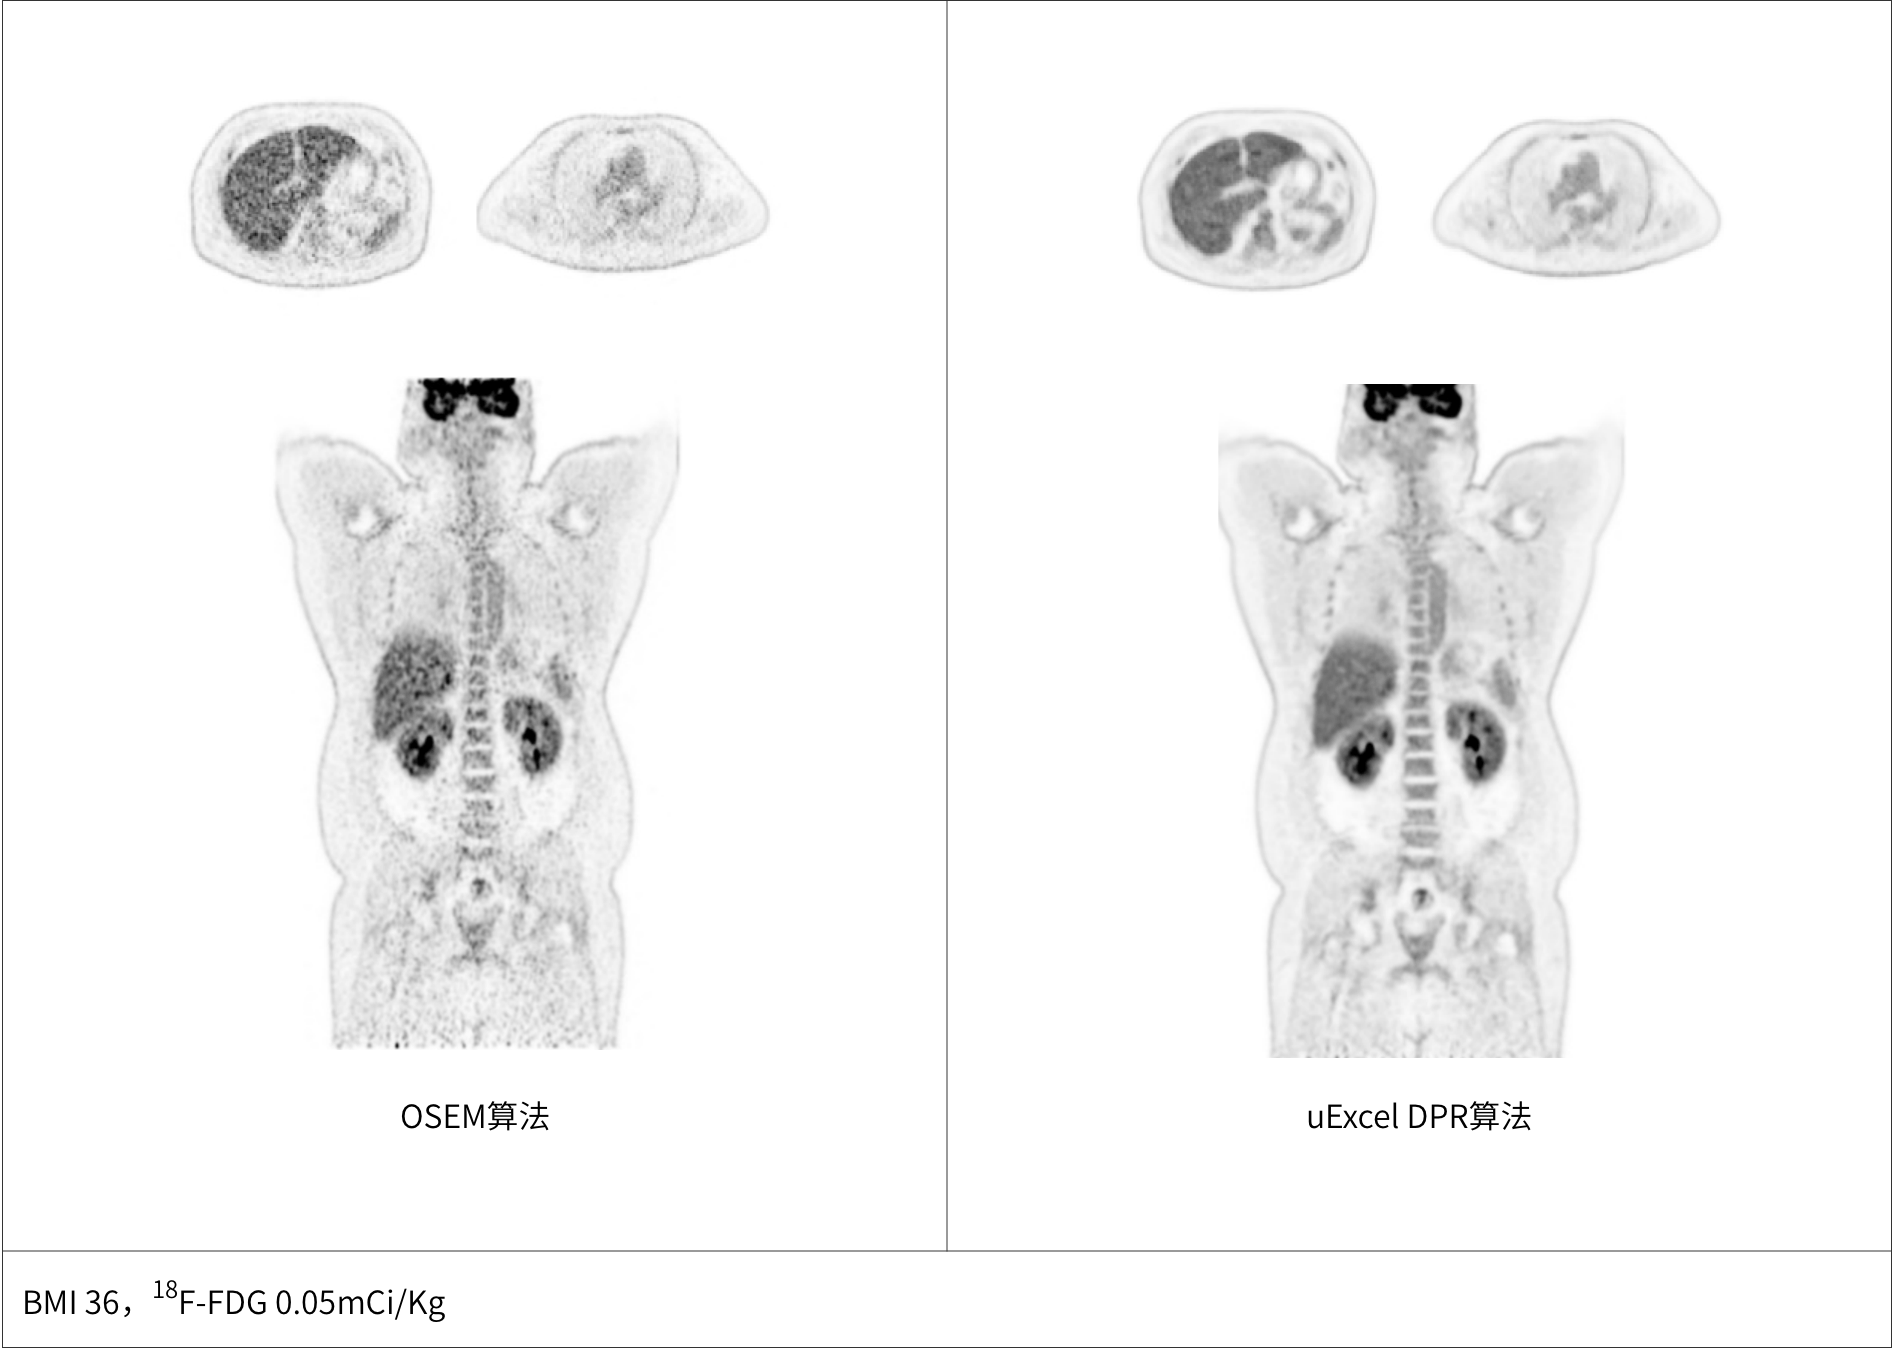

兼顾噪声、对比度、分辨率等多维度进行分布渐进式学习优化

极低噪声、高对比度uEXPLORER海量优质图像训练集有效保证输出结果的可靠性

同时实现图像对比度、噪声、信噪比三重优化

*uExcel DPR仅供科研使用

多个神经网络嵌入迭代重建中,加速图像收敛